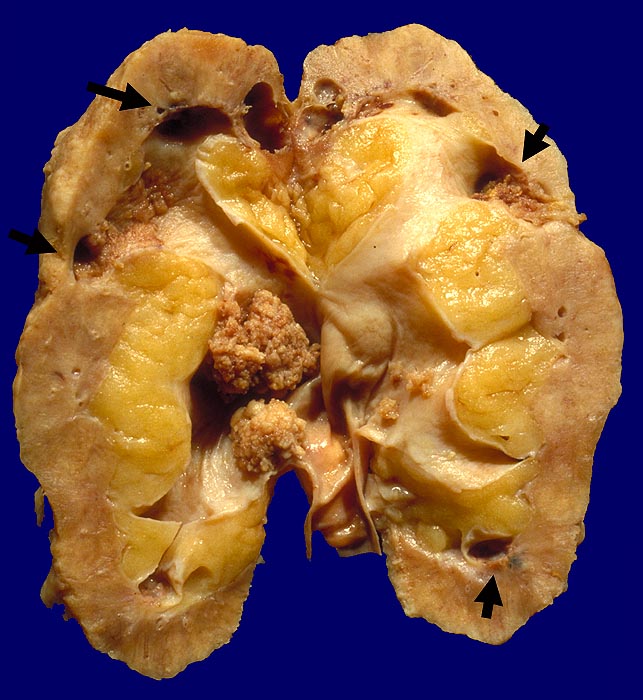

PathoPic ID 1588 - Analgetika-Nephropathie: Nierenbeckenkarzinom.

Analgetika-Nephropathie: Nierenbeckenkarzinom.

Multizentrisches polypöses Nierenbeckenkarzinom. Auf der Schnittfläche mehrere

Papillennekrosen.